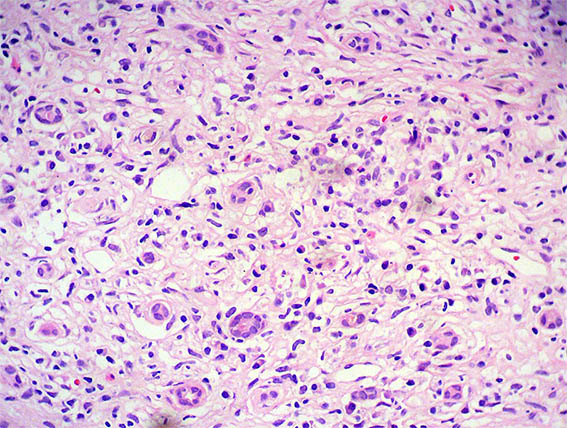

Figure 4. H&E, X400.

Figure 5. H&E, X400.

Figure 6. PAS, X400. Notorious fibrosis and tubular atrophy.